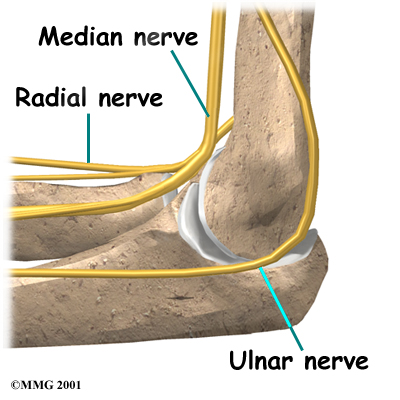

Nerves

All of the nerves that travel down the arm pass across the elbow. Three main nerves that innervate the arm, forearm, and hand begin together at the shoulder: the radial nerve, the ulnar nerve, and the median nerve. These nerves carry signals from the brain to the muscles that move the arm. The nerves also carry signals back to the brain about sensations such as touch, pain, and temperature.

Some of the more common problems around the elbow are problems of the nerves. Each nerve travels through its own tunnel as it crosses the elbow. Due to the elbow having to bend a lot, the nerves must bend as well. Constant bending and straightening can lead to irritation or pressure on the nerves within their tunnels and cause problems such as pain, numbness, and weakness in the arm and hand.